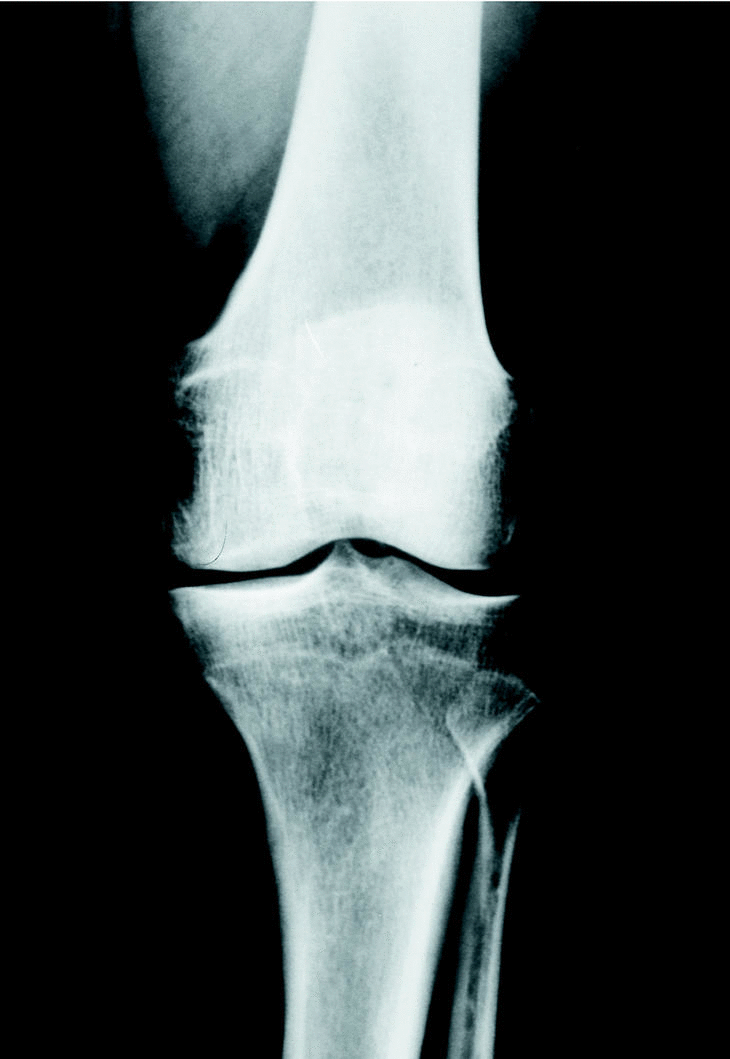

Figura 2. Genu varo artrósico en un varón de 47 años con afectación moderada del compartimento interno.

El estudio radiológico previo mostró un varo de 4,2o de media (mínimo: 0; máximo: 9). La usura del compartimento interno fue de 2 mm de media (mínimo: 1; máximo: 4) lo que traducía un pinzamiento menor del 50% del espacio articular en el 82% de ellos, correspondiente a un grado II de Ahlback6.